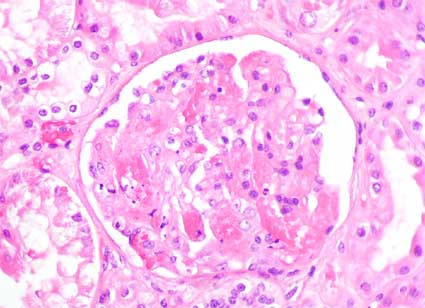

Figura 4.

H&E, X400.